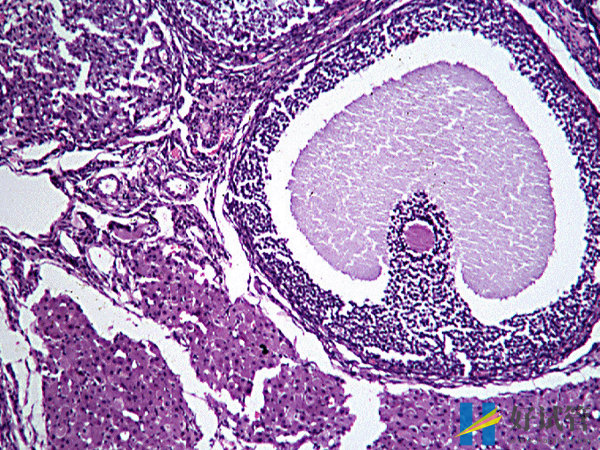

测到优势卵泡3-5天后会排卵

当优势卵泡发育成熟后,从卵巢中排出会在体内存活48小时左右,也就是两天。所以在这两天的时间里面就可以同房,这样是可以提高受孕的几率。在这48个小时之内,前二十四个小时的受精能力是最强的,后二十四个小时的受精能力就会有所下降直到死亡。而进行同房前男方也需要禁欲,这样才能提高精子的质量,进而增加受精几率。